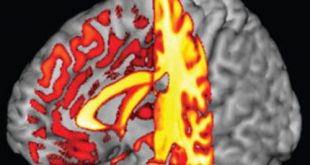

نوروسافاری | بر اساس پژوهش جدید انجام شده توسط نوروبیولوژیست های دانشکده پزشکی هاروارد، ژنی که فرآیند رشد استخوان و متابولیسم عضلات را در پستانداران تنظیم می کند، ممکن است نقش دیگری را به عنوان پیش برنده فرآیند بلوغ مغز، توانایی شناختی و یادگیری در انسان و سایر نخستی سانان …